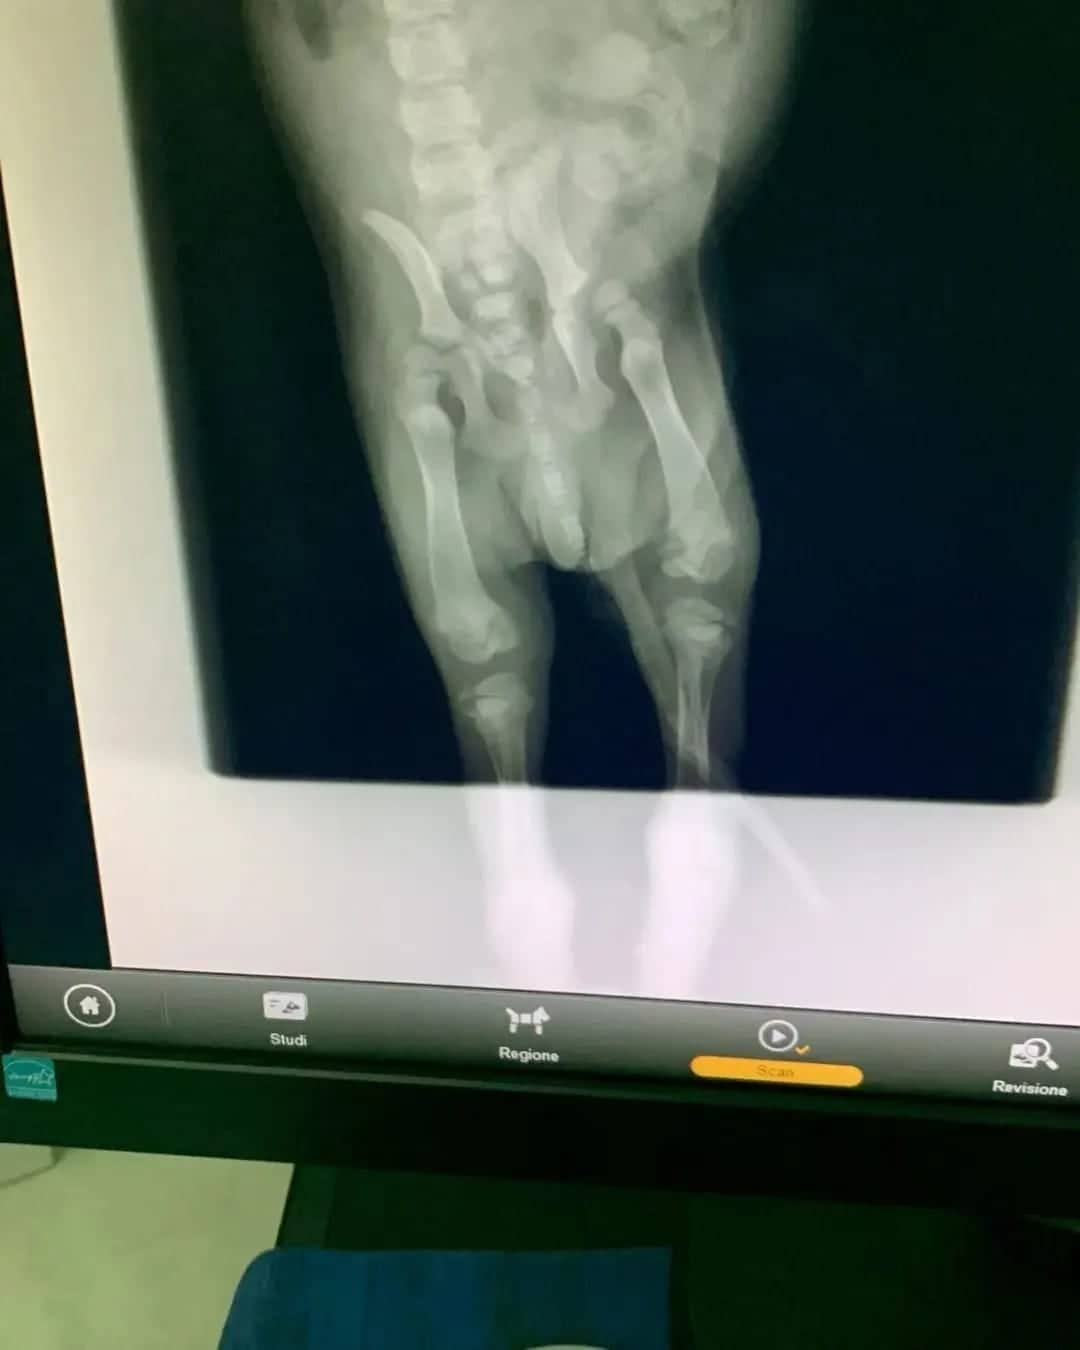

Baby Byron ha fatto le RX ma da quelle non si riscontrano danni evidenti, né alla colonna né alle zampette, quindi si presume che può essere nato con un difetto neurologico.

Occorre fare una tac (appena termina la prassi vaccinale) per capire se vi sono, e quanto sono gravi, eventuali danni al midollo. Al momento lui viene gestito come un cucciolo paraplegico.